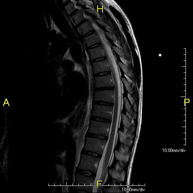

- Thoracic spine MRI

This non-invasive diagnostic procedure uses an electromagnetic field and radio waves (from a transmitter and receiver) to acquire high-definition anatomical images of the thoracic spine. It is a radiation-free procedure. Indicated for: trauma, degenerative problems, hernias, tumours.

- Lumbar spine MRI

This non-invasive diagnostic procedure uses an electromagnetic field and radio waves (from a transmitter and receiver) to acquire high-definition anatomical images of the lumbar and sacral regions. It is a radiation-free procedure. Indicated for: trauma, sciatica, herniated discs, tumours, infections.

- Thoracic + lumbar spine MRI

A non-invasive diagnostic test that involves obtaining high-definition anatomical images of the thoracic and lumbar spine using an electromagnetic field and radio waves (with transmitter and receiver). It is a radiation-free procedure. Indicated for: trauma, spinal degeneration, hernias.